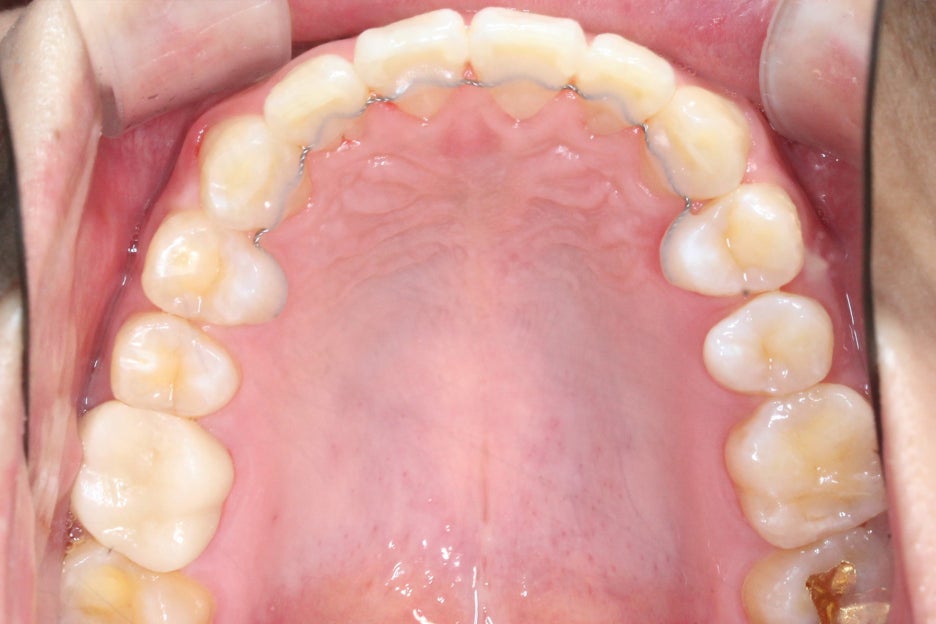

논현동치과 윗니부분교정 후 치아의 배열을 보면

바깥으로 누워있듯이 뻐드러져 있던

11번 치아가 자연스럽게

교정된 것을 확인할 수 있으며

전체적인 안모의 모양도 곡선을 그리며

U-모양으로 형성되어 있어 심미적인 모습인데요,

치아가 배열된 모습이 U-모양에 가까울수록

이상적인 안모가 될 수 있습니다.